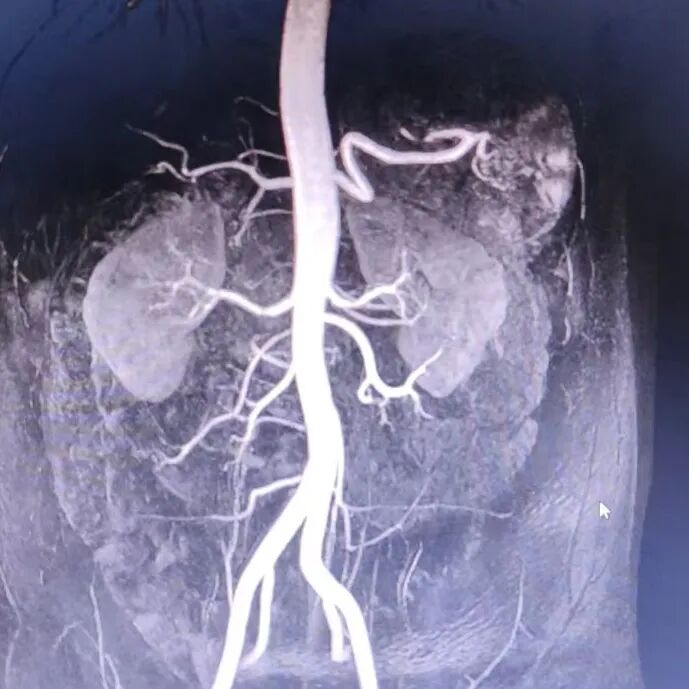

入院后继发性高血压筛查阴性;动态血压:24h平均血压:162/105mmHg,白天平均血压:160/102mmHg,夜间平均血压:171/115mmHg;肾动脉CTA检查结果示患者右肾动脉轻度狭窄,余无殊。

肾动脉CTA图